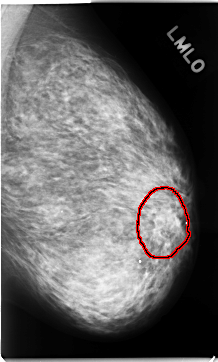

C_0130_1.LEFT_CC

FILE: C_0130_1.LEFT_CC.OVERLAY

TOTAL_ABNORMALITIES 1

ABNORMALITY 1

LESION_TYPE MASS SHAPE OVAL MARGINS ILL_DEFINED

ASSESSMENT 4

SUBTLETY 3

PATHOLOGY MALIGNANT

TOTAL_OUTLINES 1

BOUNDARY